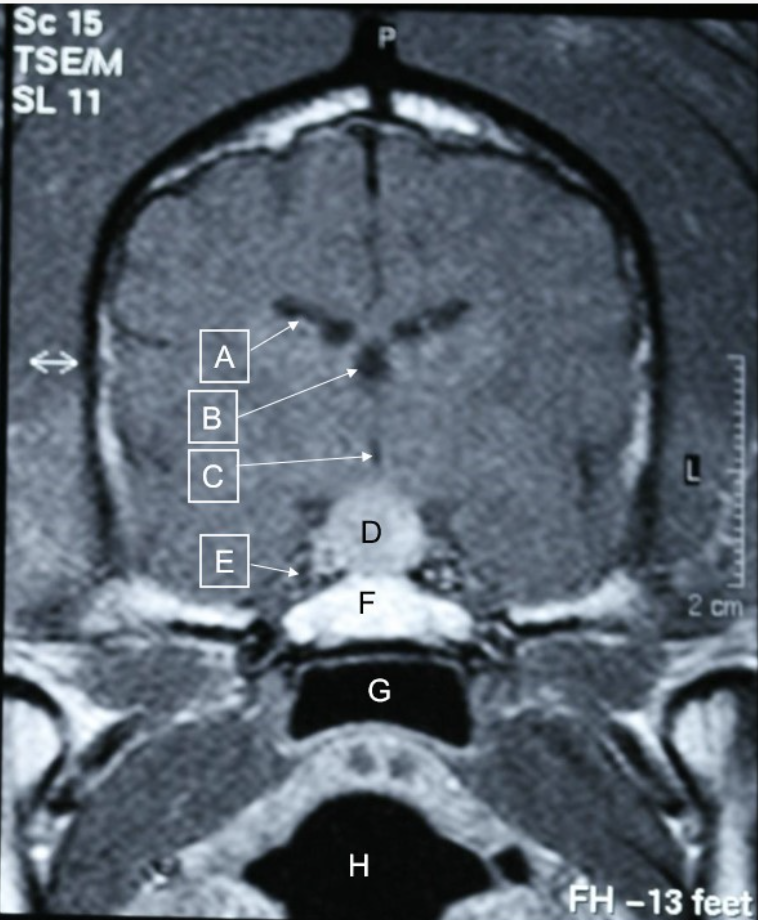

Q

Are there any pathological findings in this MRI of dogs head

A

pituitary mass at D